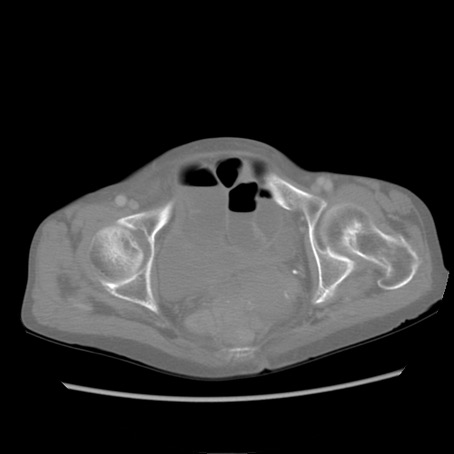

冠状断像